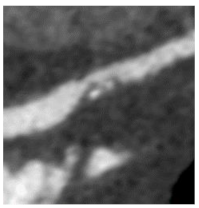

| Small spotty calcifications (SC) | Any discrete calcification ≤ 3 mm in length and occupying ≤ 90° arc when viewed on short axis. | ![]() |